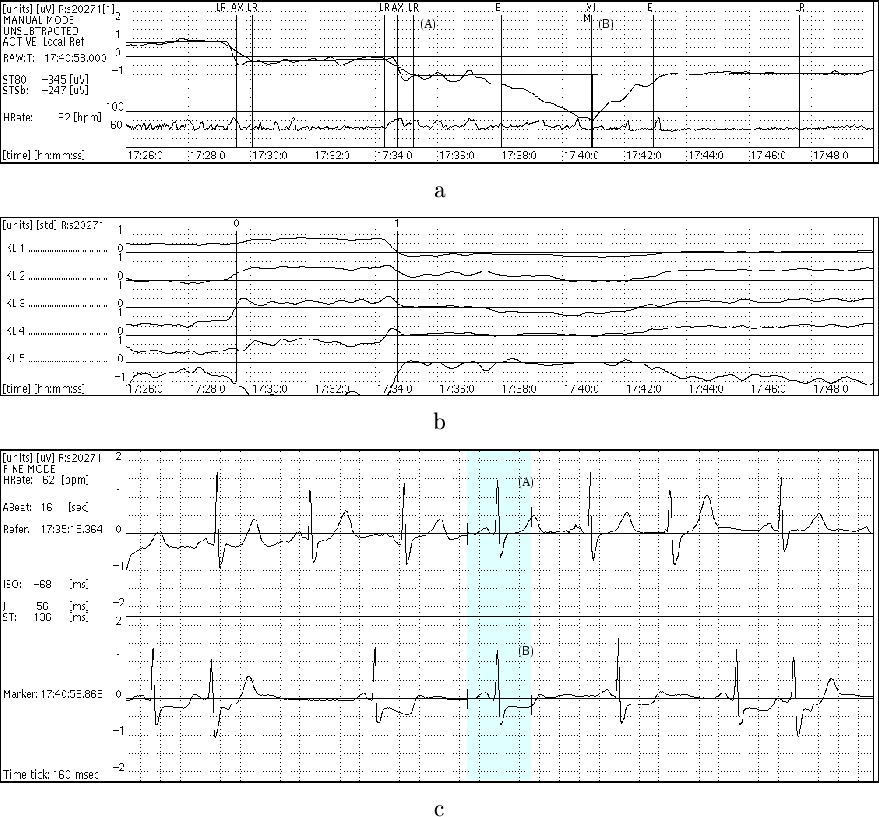

Figure:

Example of annotation of lead 1 in record s20271 from time

17:26:00 to 17:50:00. Abbreviated SEMIA's `lead', `KLT' and `data' windows

(from top to bottom) are shown. (a) ST level function (resolution: 100

V unit

)

and piecewise linearly interpolated ST reference function (above), heart rate (below),

local reference annotations (LR) defining knot points in ST level function, axis

shift annotations (AX) indicating significant ST shifts, and ST episode annotations

(BI, XI, EI) indicating significant ischaemic ST episode according to protocol A.

(b) Time series of first five (from top to bottom) QRS complex KLT coefficients

(resolution: 1 SD unit

), and markers 0 and 1 corresponding to both axis

shift annotations. (c) Original ECG signals (resolution: 1 mV unit

X 160 ms

unit

) corresponding to local reference (LR) prior to ischaemic ST episode

((A); time: 17:35:15.364) and to extrema (XI, M) of ischaemic ST episode ((B);

time: 17:40:58.868), where centre heart-beats are time-averaged heart-beats over

16 s

|